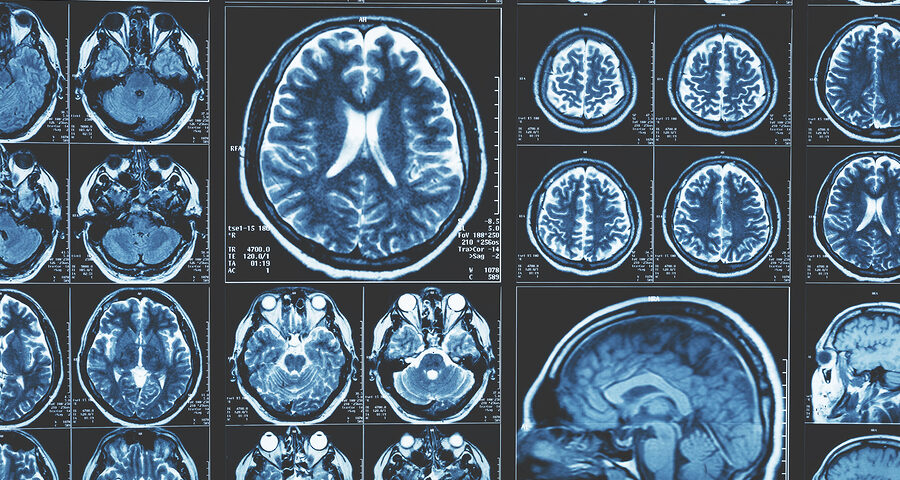

September 11, 2025Sleep disorders impact millions globally, often leaving patients and families searching for answers. When sleep issues involve the brain, neuroradiology offers valuable insights through advanced imaging techniques. This specialized field enables the diagnosis and treatment of brain-related sleep disorders more effectively. Understanding these tools can provide reassurance and clarity during the diagnostic process.

The field of Neuroradiology is the study of the brain, spine, and nervous system through advanced imaging technology. Specialists in this field analyze scans to identify structural changes, abnormalities, or patterns that help explain neurological symptoms. This expertise plays a role in diagnosing and understanding various neurological conditions. By using precise imaging techniques, neuroradiologists provide insights that guide treatment decisions.

When it comes to sleep-related brain disorders, neuroradiology helps uncover how brain structure and function might contribute to sleep problems. Imaging studies can detect issues that other tests might overlook, offering a clearer understanding of the underlying causes. Different imaging methods are used, each providing a unique perspective on brain health. Your doctor will select the most suitable approach based on your symptoms and medical history.

Neuroradiology utilizes various imaging techniques to examine the brain and spinal cord for underlying causes of sleep disorders. Each method offers unique insights into the structures and functions that impact sleep. Here are some of the most common imaging techniques used:

- Magnetic Resonance Imaging (MRI) is used to assess brain structure in sleep disorders by producing detailed images to detect issues like tumors or abnormalities in sleep-regulating regions.